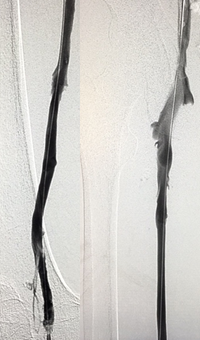

Pharmacomechanical revascularization of extensive iliofemoral thrombus

60 year old female presented with 4 weeks calf pain 1 week swelling.

Procedural steps

• Power Pulse delivery 10mg tPA

• 20 minute dwell time

• ZelanteDVT runtime 415 seconds

• Total case time 90 minutes

Xray of Iliofemoral thrombus pre-treatment and Power Pulse™ delivery

Iliofemoral thrombus pre-treatment (left) and Power Pulse delivery (right)

Xray of veins post-ZelanteDVT mechanical thrombectomy.

Post-ZelanteDVT  Mechanical Thrombectomy

Xray of veins post-ZelanteDVT runtime 415 seconds.

Post-ZelanteDVT runtime 415 seconds

Images Courtesy of Charles Wyble M.D. – Vascular Surgical Associates, Marietta, Georgia – January 5, 2016